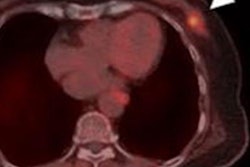

Lu-177 OncoFAP-23 is a new small molecule ligand under development for targeted radionuclide therapy in various cancers. It is designed to bind to fibroblast activation protein (FAP) in solid human malignancies where it delivers radiation to kill cancer cells while sparing normal tissue.